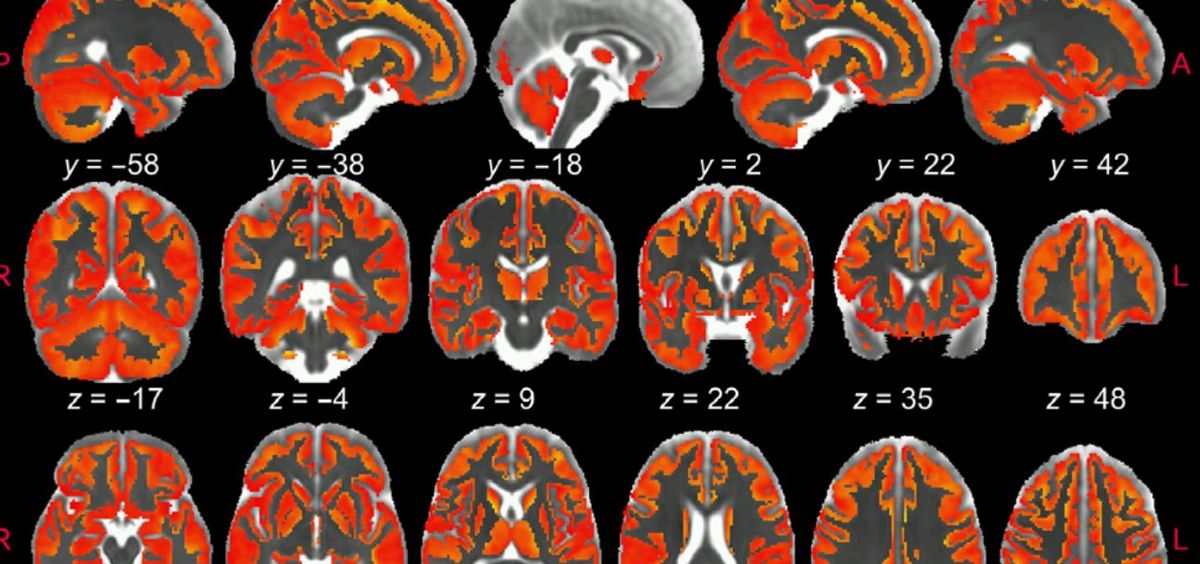

Una investigación ha permitido visualizar por primera vez y con gran detalle la inflamación cerebral utilizando Resonancia Magnética Ponderada por difusión. Esta destallada radiografía de la inflamación no puede obtenerse con una resonancia magnética convencional, sino que requiere secuencias de adquisición de datos y modelos matemáticos especiales.

La investigación, cuya primera autora es Raquel García-Hernández, demuestra que la Resonancia Magnética ponderada por difusión puede detectar de forma no invasiva y diferenciada la activación de la microglía y los astrocitos, dos tipos de células del cerebro que están en la base de la neuroinflamación y su progresión.

Frente a estos inconvenientes, la resonancia magnética ponderadapor difusión tiene la capacidad única de obtener imágenes de la microestructura cerebral in vivo de forma no invasiva y con alta resolución, al capturar el movimiento aleatorio de las moléculas de agua en el parénquima cerebral para generar contraste en las imágenes de resonancia magnética.

En este estudio, los investigadores del Instituto de Neurociencias (CSIC-UMH) han desarrollado una "estrategia innovadora" que permite obtener imágenes de la activación de la microglía y de los astrocitos en la materia gris del cerebro mediante resonancia magnética ponderada por difusión (dw-MRI).

"Es la primera vez que se demuestra que la señal de este tipo de resonancia magnética (dw-MRI) puede detectar la activación microglial y astrocitaria, con huellas específicas para cada población de células. Esta estrategia que hemos utilizado refleja los cambios morfológicos validados post mortem por inmunohistoquímica cuantitativa", señalan los especialistas en un comunicado.

Este trabajo ha logrado demostrar también el valor traslacional del enfoque utilizado en una cohorte de humanos sanos a alta resolución, "en la que se realiza un análisis de reproducibilidad".

"La asociación significativa con patrones de densidad de microglía conocidos en el cerebro humano apoya la utilidad del método para generar biomarcadores de glía fiables. Creemos que caracterizar, mediante esta técnica, aspectos relevantes de la microestructura tisular durante la inflamación, de forma no invasiva y longitudinal, puede tener un tremendo impacto en nuestra comprensión de la fisiopatología de muchas afecciones cerebrales, y puede transformar la práctica diagnóstica actual y las estrategias de seguimiento del tratamiento de las enfermedades neurodegenerativas", destaca de Santis.